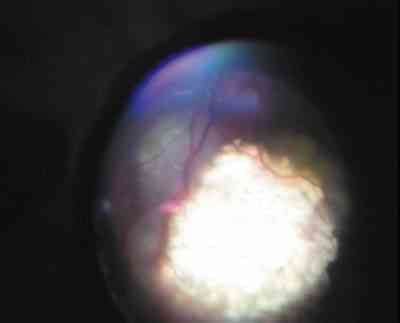

Figura 6. Reactivación de un retinoblastoma tras calcificación total por quimioterapia, tratado con placa radiactiva.

29-07.jpg (6282 bytes)

Figura 7. Regresión de la tumoración tras el tratamiento con rutenio.

Durante la cirugía el radiofísico cuantifica la emisión de radiación. El niño permanece ingresado hasta que se retira la placa, que suele ser a las 24-48 horas según la altura tumoral. En algunos niños la conjuntiva se mantiene quemótica e isquémica durante algunas semanas. En nuestra experiencia la respuesta de los retinoblastomas a las placas epiesclerales de Ru-106 ha sido espectacular, con claros signos de remisión a partir de la segunda semana del tratamiento, y sin complicaciones valorables hasta el momento.